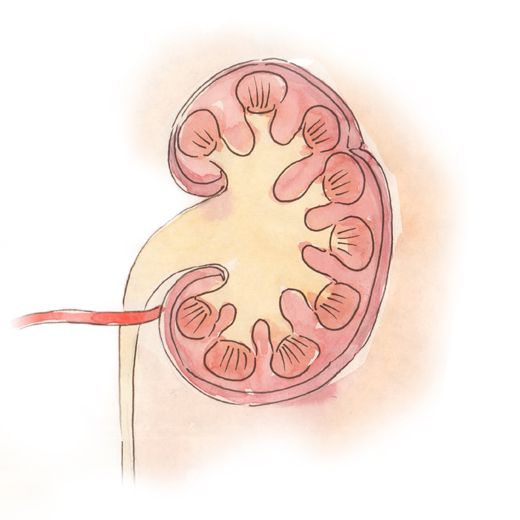

Рефлюксирующий мегауретер: Визуализация и медицинские изображения

Раздел: Фотопуть к знанию